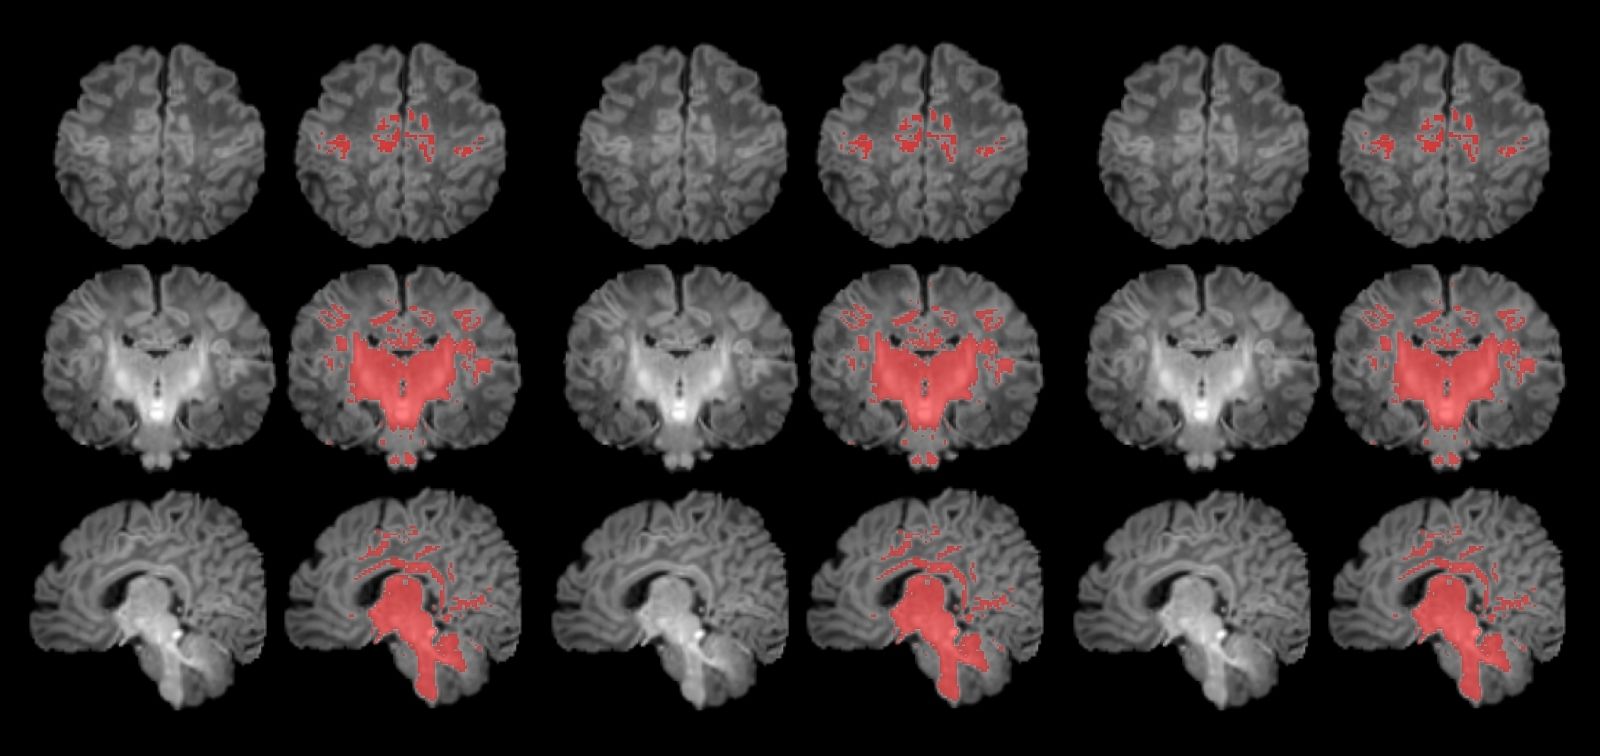

La mielinización es un proceso clave en la maduración del cerebro, en que la mielina recubre las conexiones neuronales y las hace eficientes para la transmisión de información. Los recién nacidos de madres expuestas a niveles más altos de partículas finas en suspensión durante el embarazo muestran una mielinización más lenta en esta etapa tan precoz de la vida.

En este sentido, según explica Gerard Martínez-Vilavella, investigador de la Unidad de Resonancia Magnética del Servicio de Radiología del Hospital del Mar, integrado en la red dibi, y del Instituto de Investigación del Hospital del Mar, “en el estudio vemos que el proceso de mielinización, un indicador de maduración cerebral que avanza progresivamente con el tiempo, presenta un ritmo más lento en los recién nacidos más expuestos a PM2.5 durante el embarazo”.

Para llevar a cabo el estudio se reclutó a mujeres embarazadas en seguimiento en el Hospital Clínic Barcelona, el Hospital de Sant Pau y el Hospital Sant Joan de Déu. Se monitorizaron los niveles de contaminantes atmosféricos a los cuales estaban expuestos durante la gestación y, después del parto, se seleccionó a 132 recién nacidos. A estos se les realizó una resonancia magnética antes de cumplir el primer mes de vida para observar el grado de maduración cerebral según sus niveles de mielinización.

Los resultados muestran una correlación clara entre una mayor exposición materna a PM2.5 durante el embarazo y una menor mielinización en el cerebro de los recién nacidos

Los resultados muestran una correlación clara entre una mayor exposición materna a PM2.5 durante el embarazo y una menor mielinización en el cerebro de los recién nacidos.

“La contaminación atmosférica, concretamente las PM2.5, se asocia con una alteración en el proceso de mielinización, un mecanismo esencial de maduración cerebral. Por ello hay que continuar controlando la contaminación y estudiar cómo esta ralentización puede influir en el desarrollo posterior del cerebro de los niños y niñas”, expresa Martínez-Vilavella.

El trabajo también indica que este efecto responde a la combinación de los diferentes elementos que forman las PM2.5, sin que se pueda identificar un único elemento como responsable.